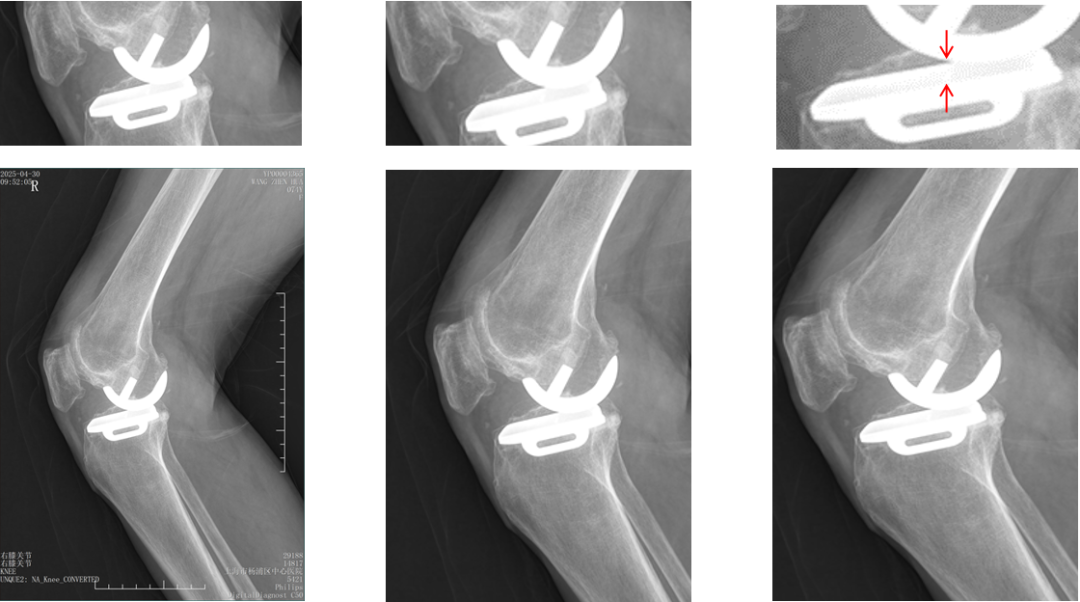

病例展示3

病例3:Bearing 陈旧性前脱位2年

病例3:Bearing 陈旧性前脱位的处理

病例展示4

病例4:内侧OxfordUKA术后6.5年外侧进展性OA

病例4:Bi-UKA术后

病例4:Bi-UKA术后Bearing 后脱位的处理